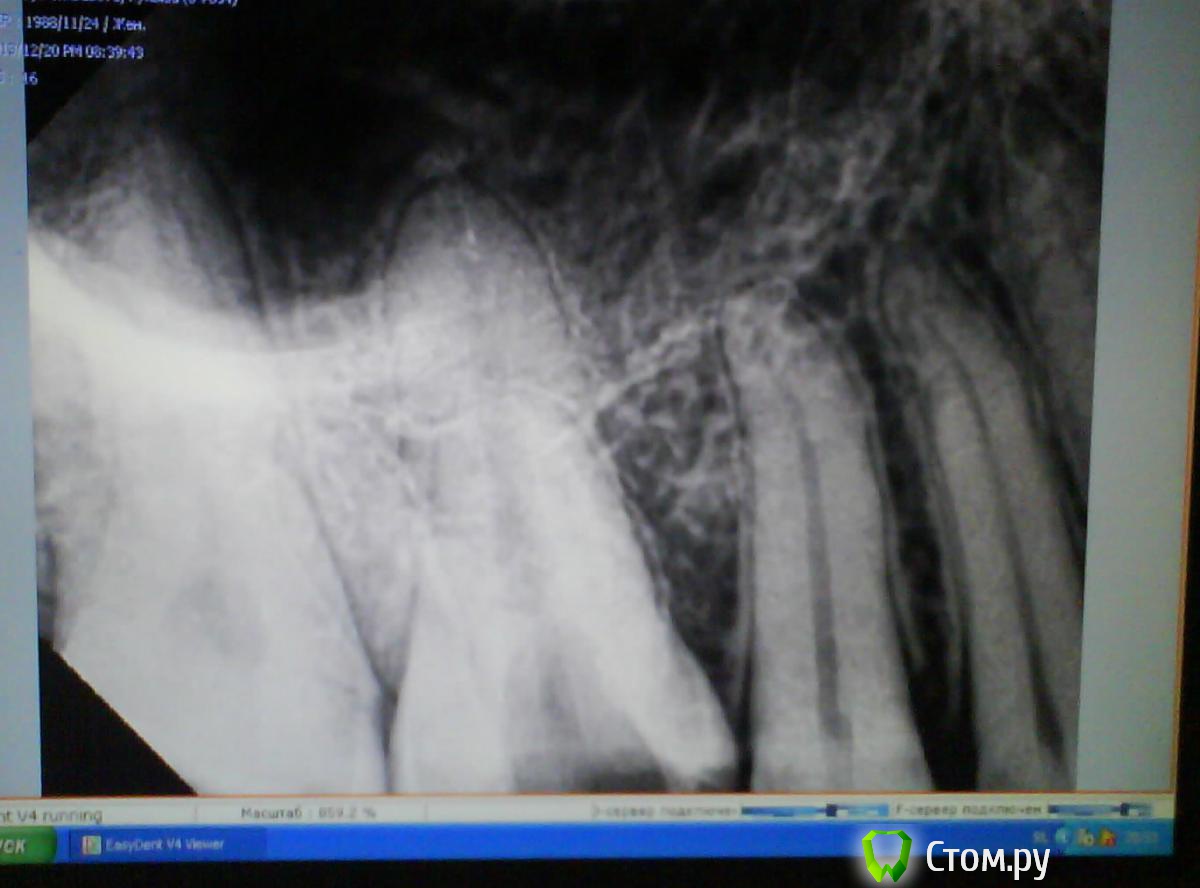

Scathach Опубликовано 20 декабря, 2013 Автор Поделиться Опубликовано 20 декабря, 2013 Дорогие докторы, выкладываю снимки. Прошу прощения за качество, пришлось шпионски снимать на телефон) Другой стоматолог сказала, что ничего криминального не во рту, ни на снимке не наблюдает.Высказала варианты: 1) корень зуба заходит в гайморову пазуху2) есть-таки маааленький хронический периодонтит3) разыгрался травматический периодонтит из-за кривой пломбы За три дня в открытом состоянии вроде стало чуточку полегче, но в целом картина прежняя - пока зубом я не жую, он остро не болит, но много раз в день возникают странные ощущения в десне, её как бы распирает немного изнутри и зуб кажется "больше" других, потом это пропадает. При постукивании зуб не болит вообще, на горячее не реагирует. Боль только когда сильно смыкаются зубы при жевании. И зуб, и десна по ощущениям (языком) намного теплее, чем "соседи". Десна при нажатии болит точно над зубом (высоко, там где уже чувствуется кость и начинается ткань щеки). Есть что-то типа маленькой болезненной штучки в этом месте, если пощупать пальцем, но никакого открытого свища и пр. нет. Ссылка на комментарий

red_butler Опубликовано 21 декабря, 2013 Поделиться Опубликовано 21 декабря, 2013 Ничего страшного не увидел, как можно скорее долечивайте зуб. Зуб оставлять открытым нельзя, происходит массивное обсеменение корневых каналов микроорганизмами из слюны. Найдите стоматолога эндодонтиста владеющего современными протоколами лечения корневых каналов Ссылка на комментарий